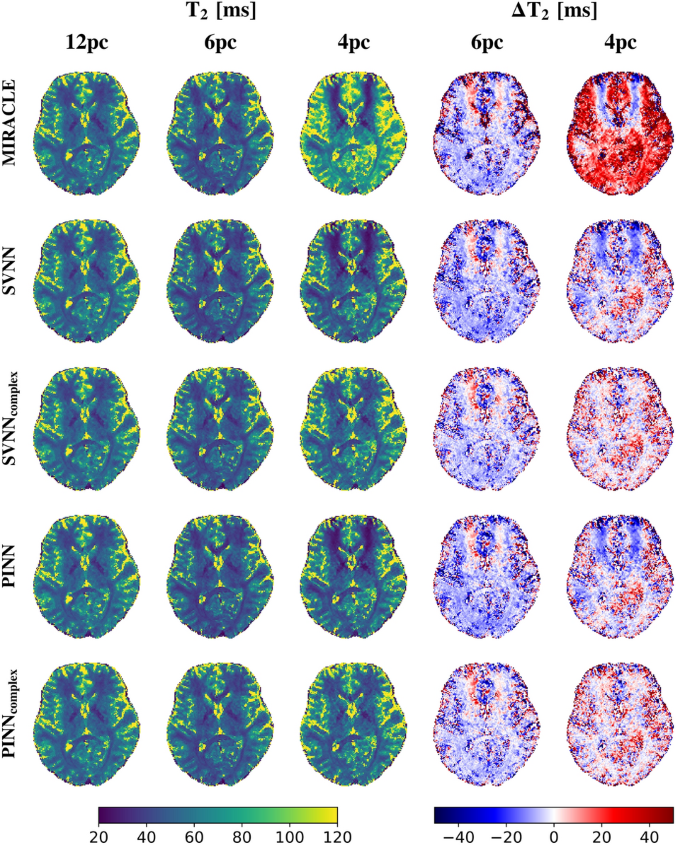

Consistent with the in silico results presented in Fig. 5, the trained complex-based DNNs demonstrate enhanced robustness to off-resonances for in vivo \(T_1\) (cf. Fig. 6) and \(T_2\) (cf. Fig. 7) relaxometry, in particular for a low number of phase cycles. At 12 phase cycles, the \(T_1\) and \(T_2\) maps of all investigated relaxometry frameworks appear very similar, while considerable differences arise in case the number of phase cycles is reduced to 4. In that case, both MIRACLE and standard magnitude-based DNNs show distinct regional patterns of pronounced under- and overestimations in \(T_1\) and \(T_2\) due to off-resonance sensitivity, in particular in frontal brain regions close to the sinuses reflecting the underlying inhomogeneities in \(B_0\) in those regions. Furthermore, MIRACLE tends to systematically underestimate \(T_1\) (cf. Fig. 6) and overestimate \(T_2\) (cf. Fig. 7) globally in brain tissue for \(N_{pc}=4\). The magnitude-based DNNs exhibit a tendency to systematically overestimate \(T_1\) for \(N_{pc}=4\), while no general systematic bias in the \(T_2\) estimates can be observed, but off-resonance-related artifacts persist. The complex-based DNNs achieve further improvement and effectively eliminate off-resonance-related artifacts and related systematic biases, especially at 4 phase cycles. Also in case of 6 phase cycles, the complex-based DNNs appear still superior to MIRACLE and magnitude-based DNNs with reduced absolute differences relative to the 12 phase cycle reference, e.g. in global WM.

Performance of complex-based DNN versus MIRACLE and magnitude-based DNN in vivo \(T_2\) estimation in case of accelerated pc-bSSFP acquisitions with only 6 and 4 phase cycles in comparison to the standard protocol with 12 phase cycles. A representative axial slice of the in vivo whole-brain \(T_2\) predictions of an unseen test subject obtained with 12, 6, and 4 phase cycles is shown in the first, second, and third column for each framework (MIRACLE, SVNN, \(SVNN_{complex}\), PINN, \(PINN_{complex}\), from top to bottom), respectively. The absolute differences \(\Delta T_2 = \hat{T}_2 - \hat{T}_{2, 12 pc}\) between the parameter predictions with 6 and 4 phase cycles relative to the reference with 12 phase cycles are shown in the fourth and fifth column, respectively.